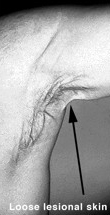

PXE often causes visible changes in the skin. These changes vary from person to person. The earliest changes are usually in the skin on the sides of one's neck. Small lesions called papules may develop (see Figure 1).They may resemble a rash or have a "cobblestone" appearance. These lesions in the skin can progress slowly and unpredictably, from the neck downward. With time, the lesions can come together to form plaques, and the skin becomes loose and wrinkly (see Figure 2).

Skin signs of PXE can occur in young children. The areas of the body that are most affected are those which bend and flex. The neck, the underarms, the skin on the inside of the elbows, the groin, and the skin behind the knees may be progressively affected, leading to loose folds in these areas. Some of these changes may be alleviated by reconstructive or plastic surgery. Lesions may also appear on mucous membranes such as the inside of the lower lip or lining of the rectum or vagina but cause no symptoms or cosmetic abnormality.It is possible to have PXE and not have any apparent skin lesions. In some individuals, careful examination of the skin by a dermatologist does not reveal any visible lesions, but a positive biopsy indicates the diagnosis of PXE.